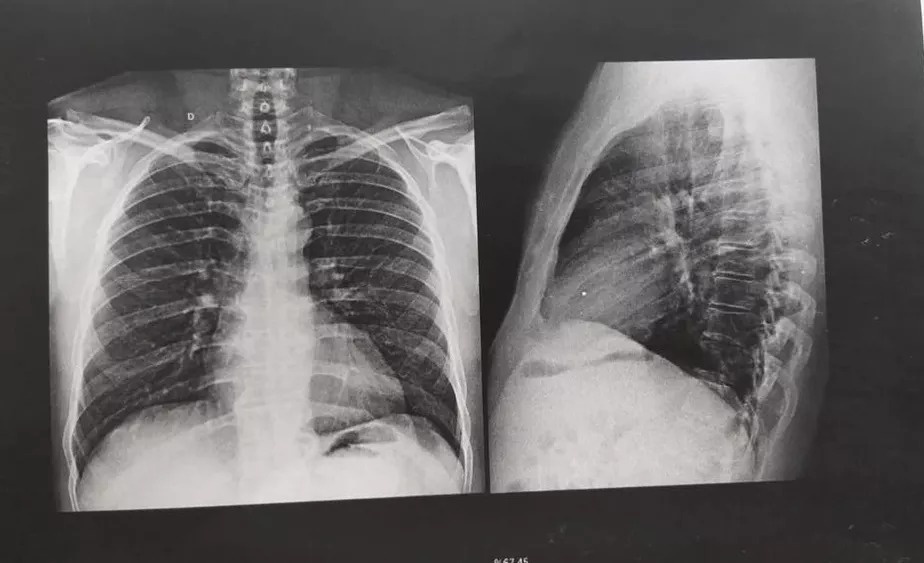

A Justiça deferiu uma liminar determinando que o Estado e a prefeitura disponibilize uma vaga de UTI para Cícero Henrique Luna da Silva, de 51 anos, que está internado em estado grave na UPA (Unidade de Pronto Atendimento) Morada do Ouro, em Cuiabá-MT, desde quarta-feira (20), após sofrer um infarto.

O laudo médico apontou ainda que pelo estado grave de Cícero, ele precisa realizar um cateterismo e ser transferido para uma UTI.